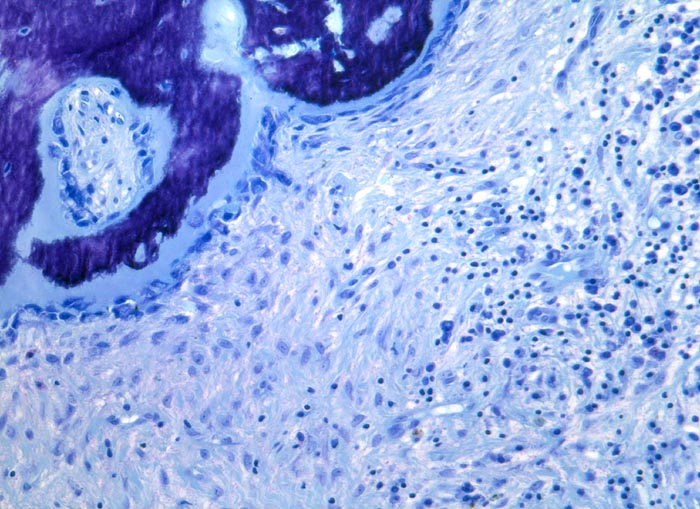

chronische Osteomyelitis

Entzündung infektiös

Knochen, Wirbelsäule

Schmerzen im mittleren Brustwirbelsäulenbereich. Destruktion der BWK VIII und IX unter Einschluss des Diskus intervertebralis. Der Prozess wird ausgeräumt.

Differentialdiagnostisch kommen bei einer Wirbelkörperdestruktion ein Lymphominfiltrat, Metastasen oder spezifische Osteomyelitiden in Frage (Tb).

Histologie

100